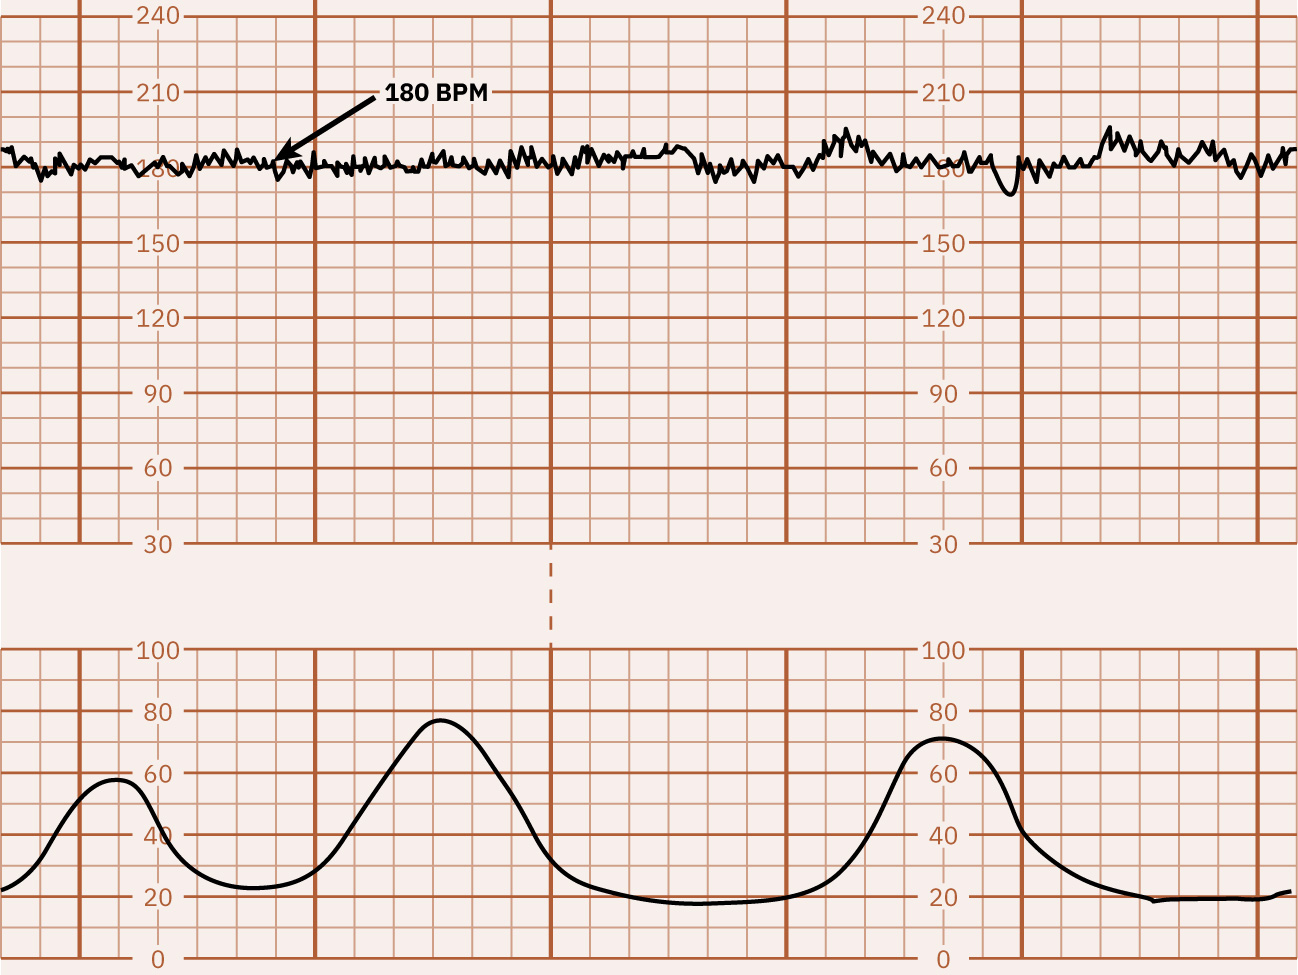

• 기저선: 주요 주기성 변화와 현저한 변이도를 제외한 10분 평균 FHR로, 보통 5-bpm 간격으로 기록합니다. 빈맥은 10분 이상 160 bpm 초과, 서맥은 10분 이상 110 bpm 미만입니다.

약 180 bpm 기저선 빈맥을 보여주는 FHR 추적 예시 Illustration reference: OpenStax Maternal-Newborn Nursing Ch.16.1.

• 기저선을 확인하고 빈맥(10분 이상 >160) 또는 서맥(10분 이상 <110)을 식별합니다.

• 기저선 빈맥에서는 모체(감염/발열, 불안, 탈수, 니코틴, 일부 약물, 갑상선 맥락)와 태아(저산소증, 감염, 빈혈, 미숙성, 부정맥) 기여 요인을 검토합니다.

• 기저선 서맥에서는 모체(저혈압/마취 영향, 대사 원인, 일부 약물, 주요 산과 응급, 모체 맥박 오독 가능)와 태아(아두/제대 압박, 저산소증, 선천 전도 이상) 기여 요인을 검토합니다.